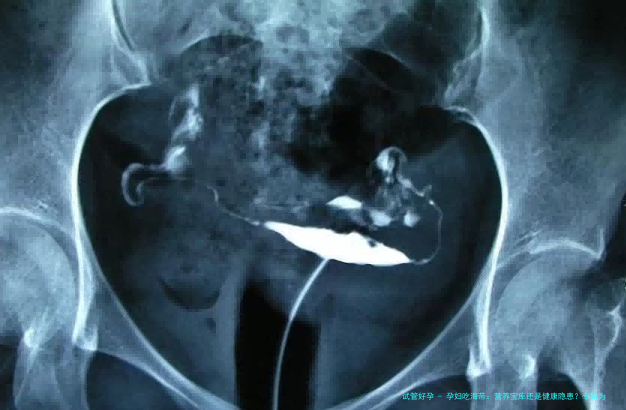

北京妇产医院2022年接诊的案例颇具警示性:一位每天喝海带汤的孕妇,孕24周时查出促甲状腺激素(TSH)异常波动。经检测,其尿碘浓度高达1200μg/L(正常范围150-250)。主治医师李敏指出:「过量碘摄入可能引发甲状腺功能紊乱,增加早产风险。」